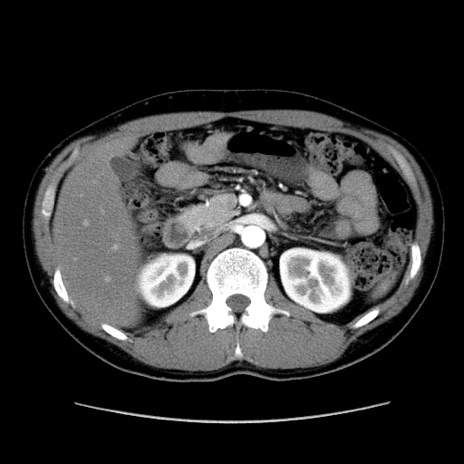

症例36(横断像)

【症例】20歳代 男性

【主訴】心窩部痛

【現病歴】今朝より上腹部痛あり。一旦軽快していたが再度出現したため救急要請。昨日夕に白身の魚を含む刺身を食べた。

【身体所見】BP 136/89mmHg、HR 74/min、BT 37.0℃、腹部:膨満、軟、心窩部に圧痛あり。反跳痛なし、筋性防御なし、腸雑音やや亢進あり。

【データ】WBC 17700、CRP 0.48